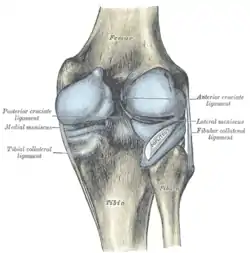

Intracapsular

The knee is stabilized by a pair of cruciate ligaments. These ligaments are both extrasynovial, intracapsular ligaments.[17] The anterior cruciate ligament (ACL) stretches from the lateral condyle of femur to the anterior intercondylar area.[13] The ACL is critically important because it prevents the tibia from being pushed too far anterior relative to the femur.[13] It is often torn during twisting or bending of the knee.[18] The posterior cruciate ligament (PCL) stretches from medial condyle of femur to the posterior intercondylar area. This ligament prevents posterior displacement of the tibia relative to the femur.[13] Injury to this ligament is uncommon but can occur as a direct result of forced trauma to the ligament.

The transverse ligament stretches from the lateral meniscus to the medial meniscus. It passes in front of the menisci. It is divided into several strips in 10% of cases.[10]: 208 The two menisci are attached to each other anteriorly by the ligament.[19] The posterior (of Wrisberg) and anterior meniscofemoral ligaments (of Humphrey) stretch from the posterior horn of the lateral meniscus to the medial femoral condyle. They pass anterior and posterior to the posterior cruciate ligament respectively.[13][10]: 208 The meniscotibial ligaments (or "coronary") stretches from inferior edges of the menisci to the periphery of the tibial plateaus.

Extracapsular

The patellar ligament connects the patella to the tuberosity of the tibia. It is also occasionally called the patellar tendon because there is no definite separation between the quadriceps tendon (which surrounds the patella) and the area connecting the patella to the tibia. [20] This very strong ligament helps give the patella its mechanical leverage [21] and also functions as a cap for the condyles of the femur. Laterally and medially to the patellar ligament the lateral and medial retinacula connect fibers from the vasti lateralis and medialis muscles to the tibia. Some fibers from the iliotibial tract radiate into the lateral retinaculum and the medial retinaculum receives some transverse fibers arising on the medial femoral epicondyle.[10]: 206

The medial collateral ligament (MCL a.k.a. "tibial") stretches from the medial epicondyle of the femur to the medial tibial condyle. It is composed of three groups of fibers, one stretching between the two bones, and two fused with the medial meniscus. The MCL is partly covered by the pes anserinus and the tendon of the semimembranosus passes under it.[10]: 206 It protects the medial side of the knee from being bent open by a stress applied to the lateral side of the knee (a valgus force).[10]: 206

The lateral collateral ligament (LCL a.k.a. "fibular") stretches from the lateral epicondyle of the femur to the head of fibula. It is separate from both the joint capsule and the lateral meniscus.[10]: 206 It protects the lateral side from an inside bending force (a varus force). The anterolateral ligament (ALL) is situated in front of the LCL.

Cruciate ligaments

Left knee-joint from behind, showing interior ligaments.